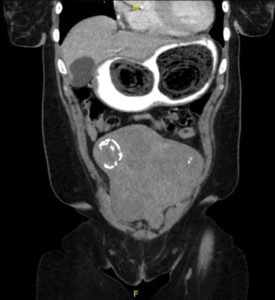

Computed tomography (CT) of the abdomen and pelvis with oral and intravenous contrast was ordered to evaluate her symptoms. The CT showed three large collections of ingested material seen as hypodense material with circular rings surrounded by the hyperdense oral contrast (see red outlines). These findings are consistent with bezoars, the largest of which measured 11.5 x 7.8 cm. There was also thickening of the gastric wall (see blue outline), most notably at the pylorus, consistent with partial obstruction.